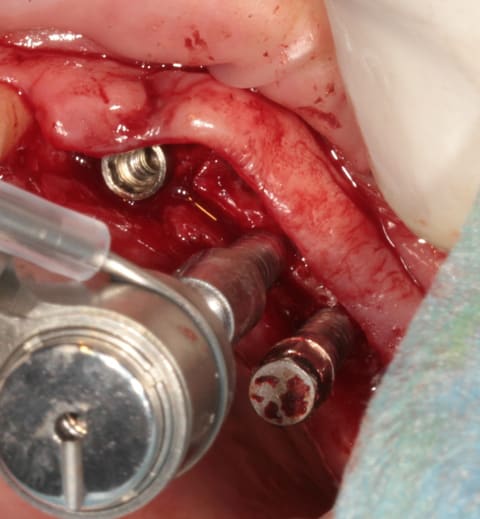

après les implants lisses coniques il faut passer aux lisses Axioms

donc Ostéotomes impactés pour mettre la corticale du sinus aux dimensions et pousser la membrane (et l'éponge)

en 25 pour le moment l'axiom lisse est de 3.4mm